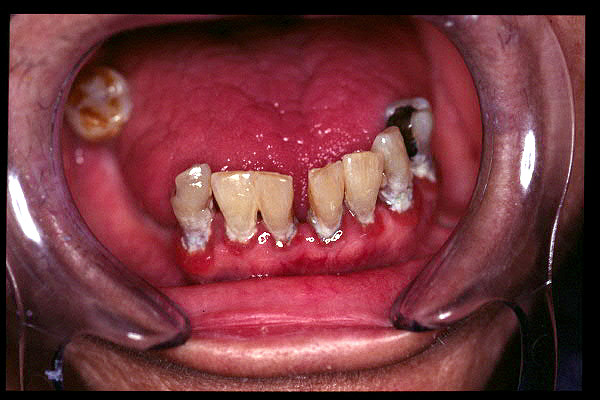

CM Caries, patología periodontal, desgaste.